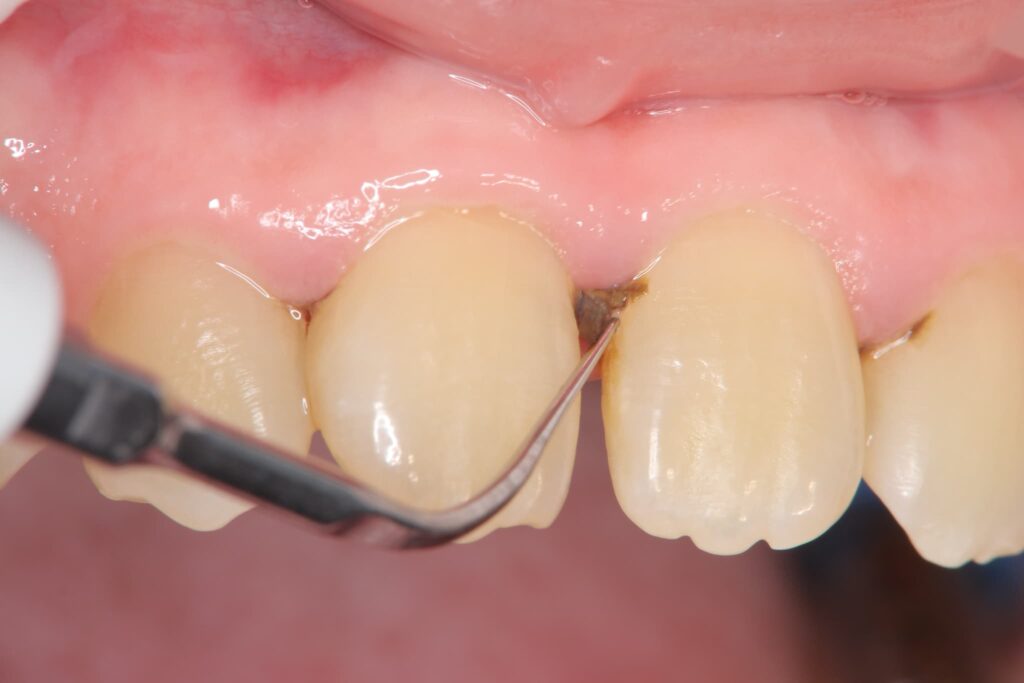

歯周病の治療のためケーリングと呼ばれる歯石除去を行っているところ

歯周病の治療方法は進行度によって異なります。早期の段階で治療を受けることで、進行を食い止めやすくなります。以下では、進行段階ごとの治療方法を詳しく解説します。

歯肉炎の治療

歯肉炎の段階では、基本的な口腔ケアとプロフェッショナルクリーニングが主な治療方法となります。歯科医院では、スケーリングと呼ばれる歯石除去が行われ、これにより炎症を抑えることができます。

軽度から中等度の歯周炎では、スケーリングに加えてルートプレーニングという処置を行います。この処置では、歯の根元を滑らかにし、細菌の再付着を防ぐことを目的としています。